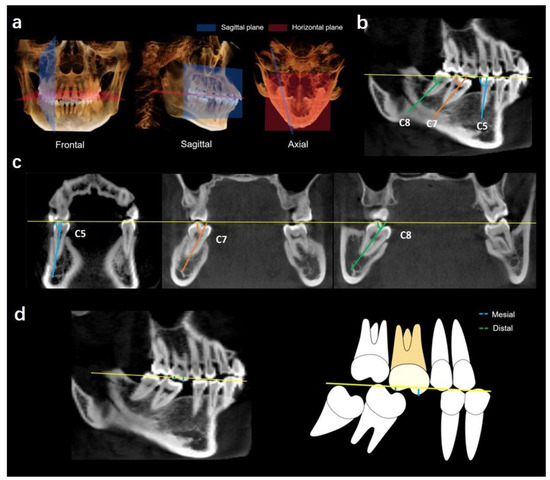

Characteristics of Spatial Changes in Molars and Alveolar Bone Resorption among Patients with Loss of Mandibular First Molars: A CBCT-Based Morphometric Study

Objectives: To investigate the characteristics of spatial changes in molars and alveolar bone resorption among patients with loss of mandibular first molars. Methods: A total of 42 CBCT scans of patients with missing mandibular first molars (3 males, 33 females) and 42 CBCT [...] Read more.

Objectives: To investigate the characteristics of spatial changes in molars and alveolar bone resorption among patients with loss of mandibular first molars. Methods: A total of 42 CBCT scans of patients with missing mandibular first molars (3 males, 33 females) and 42 CBCT scans of control subjects without loss of mandibular first molars (9 males, 27 females) were evaluated in this cross-sectional study. All images were standardized using the mandibular posterior tooth plane with Invivo software. The following indices regarding alveolar bone morphology were measured, including alveolar bone height, bone width, mesiodistal and buccolingual angulation of molars, overeruption of maxillary first molars, bone defects, and the capability of molar mesialization. Results: The vertical alveolar bone height in the missing group was reduced by 1.42 ± 0.70 mm, 1.31 ± 0.68, and 1.46 ± 0.85 mm on the buccal, middle, and lingual side, respectively (no differences among the three sides; p > 0.05). Alveolar bone width was reduced the greatest at the buccal CEJ level and the least at the lingual apex level. Mandibular second molar mesial tipping (with mean of the mesiodistal angulation = 57.47 ± 10.34°) and lingual tipping (with mean of the buccolingual angulation = 71.75 ± 8.34°) were observed. The mesial and distal cusps of maxillary first molars were extruded by 1.37 mm and 0.85 mm, respectively. Buccal and lingual defects of alveolar bone occurred at the CEJ, mid-root, and apex levels. Through 3D simulation, the second molar cannot be successfully mesialized into the missing tooth position, and the difference between the available and required distances for mesialization was the greatest at the CEJ level. The duration of tooth loss was significantly correlated with the mesio-distal angulation (R = −0.726, p < 0.001), buccal-lingual angulation (R = −0.528, p < 0.001) and the extrusion of the maxillary first molar (R = −0.334, p < 0.05). Conclusion: Both vertical and horizontal resorption of alveolar bone occurred. Mandibular second molars exhibit mesial and lingual tipping. Lingual root torque and uprighting of the second molars are needed for the success of molar protraction. Bone augmentation is indicated for severely resorbed alveolar bone. Full article